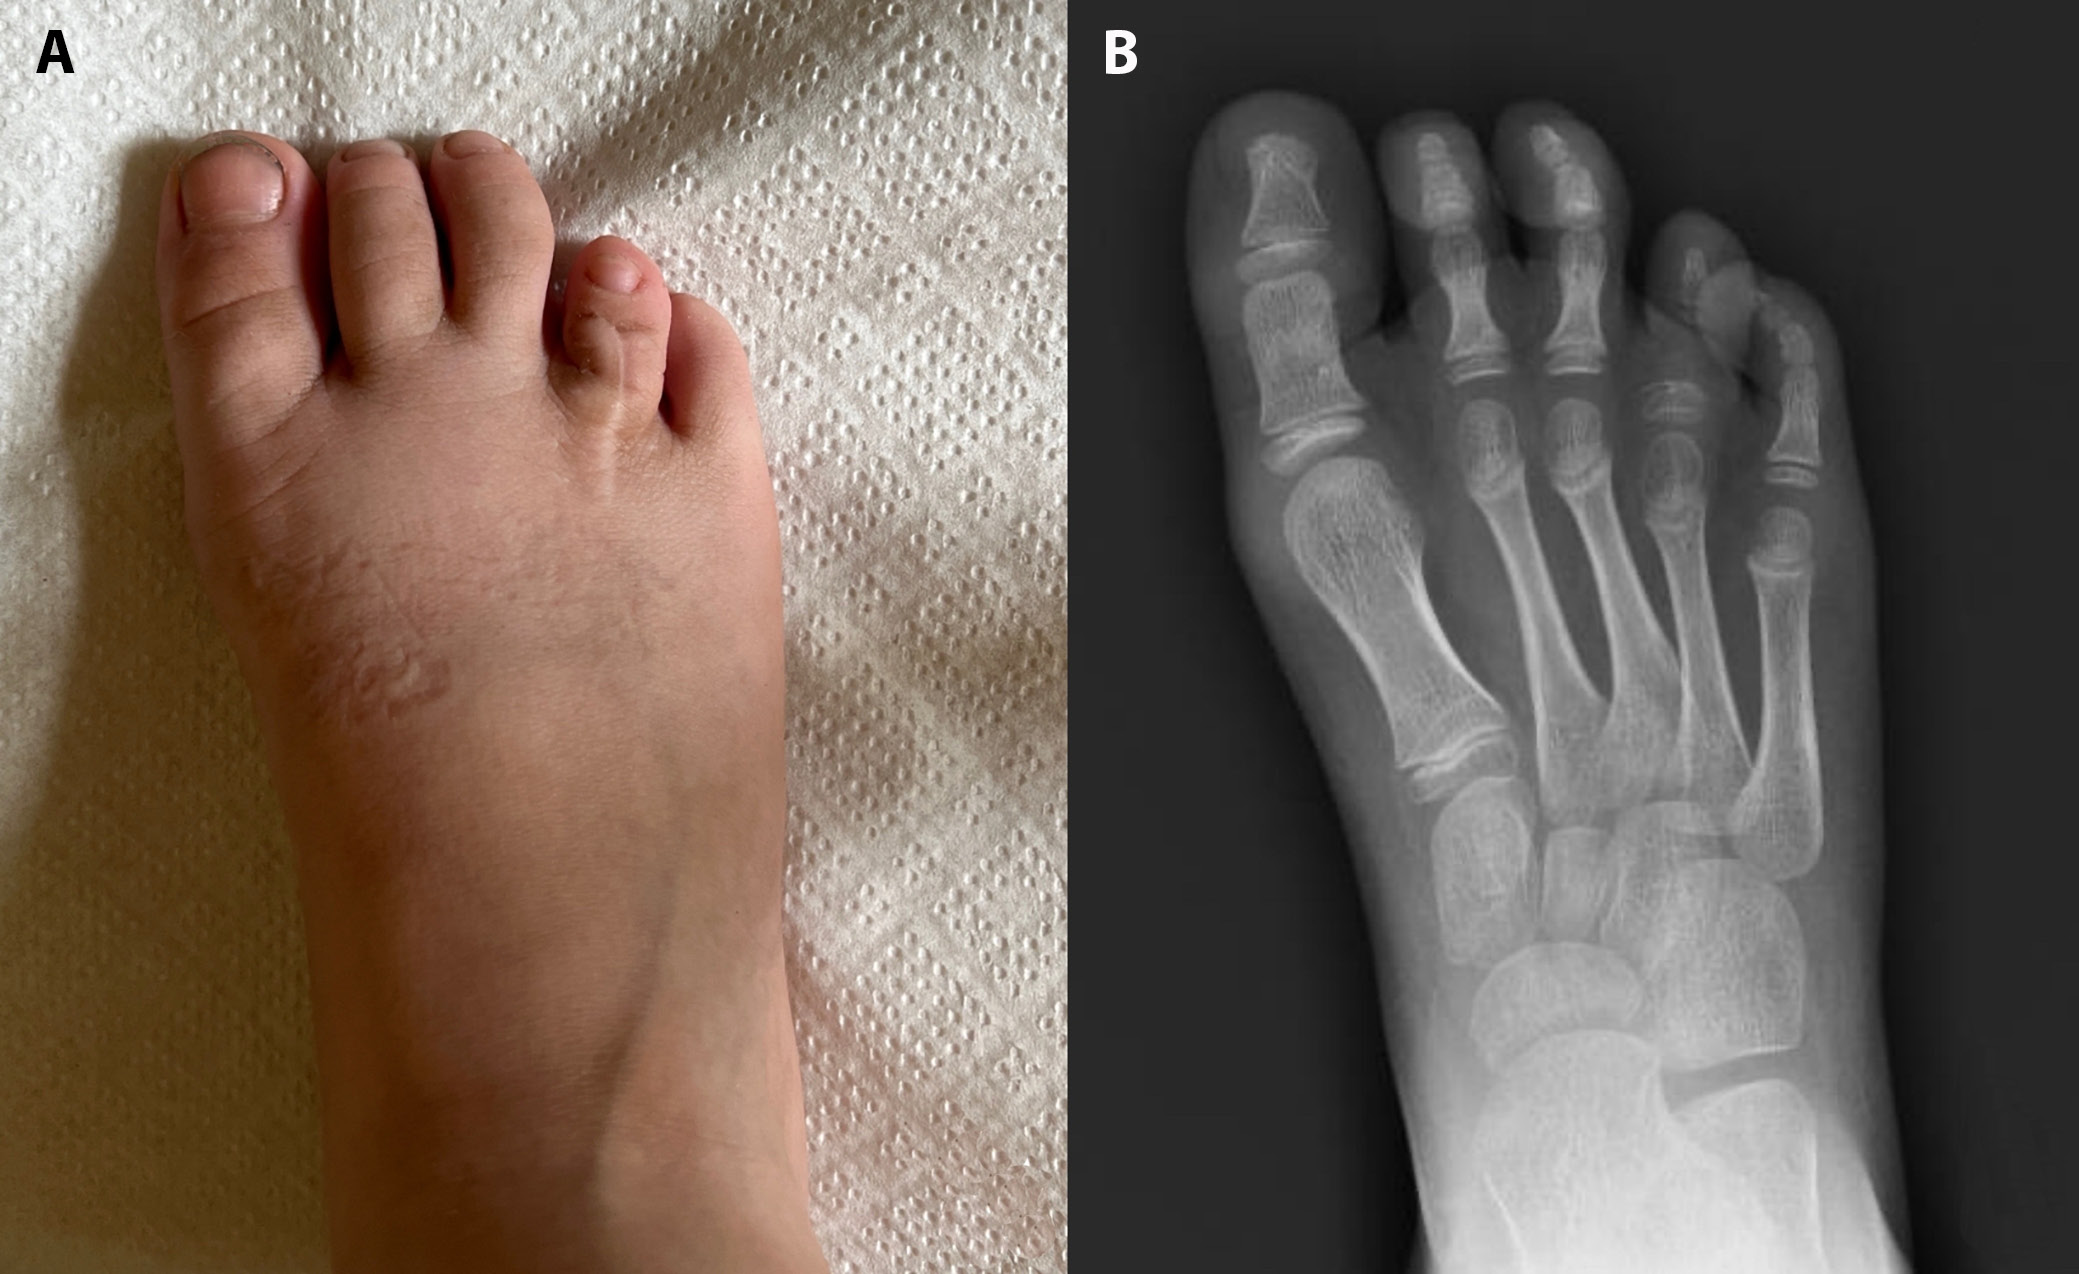

In 75% of cases, harvesting the PIP joint from the toe resulted in toe shortening, moderate in 5 patients and mild in 1 – though this did not pose a significant cosmetic concern. No patient experienced postoperative difficulties with ambulation or weight-bearing on the donor foot. However, 1 patient developed toe flaccidity after joint harvest, occasionally causing the toe to catch on footwear or when walking barefoot (Figure 4).